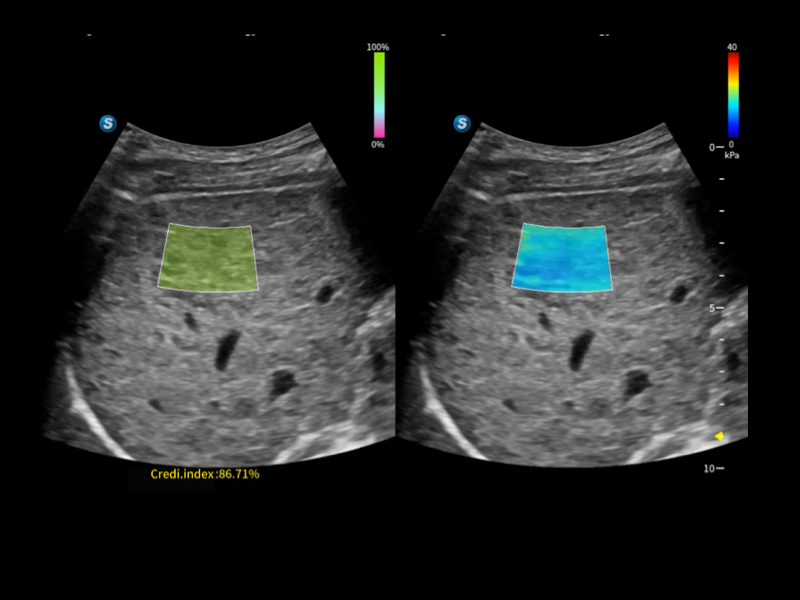

作为开立医疗全新打造的超高端旗舰超声产品,从探头抬起唤醒开启扫查到多维探头发射接收,通过先进的场成像发射、自适应聚合重建等技术,基于RF Data原始射频数据在图像生成、高端功能等方面实现突破,提供多科室综合临床解决方案。

S80 提供多样化超声成像技术,可满足不同科室的需求,在助力扫查诊断和介入治疗中发挥着重要作用。